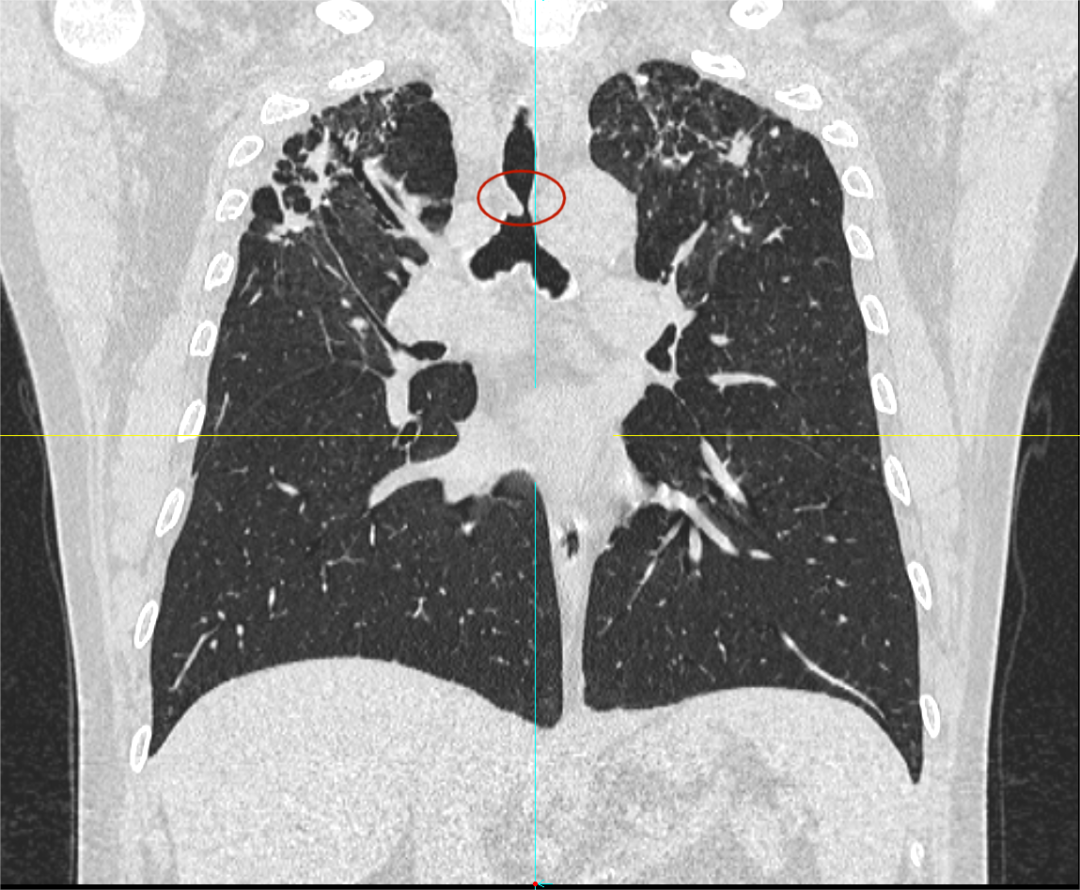

日前,患者趙先生(化名)因進(jìn)行性呼吸困難來到河南省胸科醫(yī)院尋求治療,經(jīng)檢查確診為支氣管結(jié)核導(dǎo)致氣管中下段重度瘢痕性狹窄,最窄處直徑僅約3mm,且局部軟骨環(huán)破壞、塌陷,這意味著支撐氣道的結(jié)構(gòu)遭到損毀,通氣功能嚴(yán)重受損,且因狹窄部位靠近隆突,治療操作風(fēng)險(xiǎn)極高,稍有不慎就可能導(dǎo)致大出血、氣道完全閉塞等致命并發(fā)癥。

在硬質(zhì)支氣管鏡引導(dǎo)下,手術(shù)團(tuán)隊(duì)首先對(duì)狹窄部位進(jìn)行球囊擴(kuò)張。隨后,將術(shù)前根據(jù)患者三維CT數(shù)據(jù)定制的Y型硅酮支架精準(zhǔn)覆蓋于氣管狹窄段。該支架確保與患者自身的氣道解剖結(jié)構(gòu)完美貼合,實(shí)現(xiàn)最佳支撐效果,并最大限度減少粘膜刺激增生等特點(diǎn)。支架展開后穩(wěn)定支撐于隆突及雙側(cè)主支氣管,氣道狹窄立即得到解除。